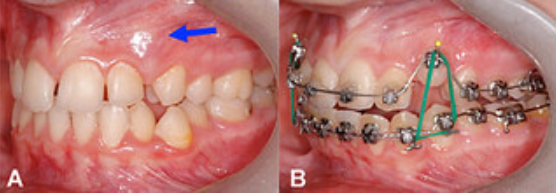

Дистопированные зубы 1.3, 2.3. Ретенированныe зубы 3.5, 4.5.

Ортодонтическое лечение с помощью брекет-системы в течении 2,5 лет

Доктор: Дейнеко Наталия Владимировна